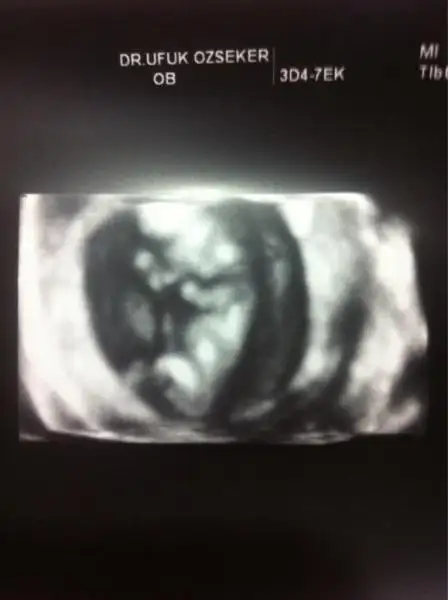

Kızlar benim bebeğimin de cinsiyetini tahmin eder misiniz ? İkili test sırasında Oğlan'a benzettim ama bana güvenme dedi ultrasonu çeken doktor. Kendi doktorum değildi. Devlette yaptırmıştım ikili testi. Çok merak ediyorum.

İlk resimde 10+2 ydik.

ikinci resimde sat 13+2 ultrason 12+5 ti. Gerçi hep sat ile ultrason uyumlu gittim. Devletteki ultrason bozdu olayı :) $IMG.webp $1401271843618.webp

Yorumlarınızı bekliyorum.